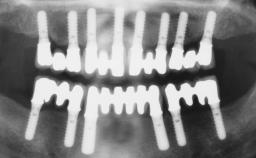

Immediate Loading of Six Implants in the Mandible and Six Implants in the Maxilla and Final Restoration with Full-Arch CAD/CAM Metal Framework FDPs Involving Digital Planning and Guided Surgery

# of Implants 12

Type of Implants One-Piece

Guided Surgery Yes

Defining Characteristics Fully edentulous upper jaw to be rehabilitated with four or more implants

Modality 6+ implants with immediate loading